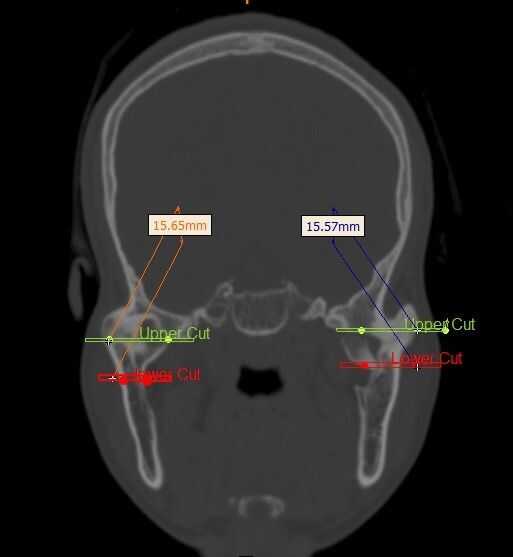

Los cortes para la extracción de hueso están marcados en las secciones coronales de la exploración del CT. Los cortes están marcados que sea lejos de la base del cráneo y el foramen mandibular. Esto es para evitar cualquier lesión en el cráneo y el cerebro durante la cirugía. Lo mismo se hace en las articulaciones de la mandíbula izquierda y derecha.